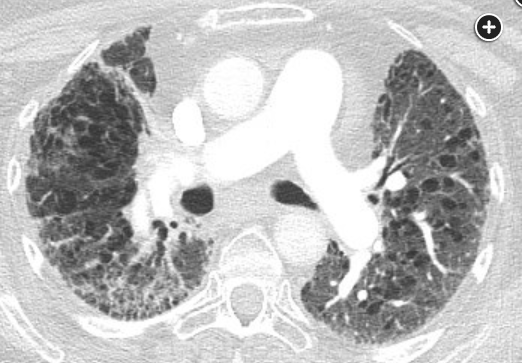

For the past 20 years, there has been an increasing appreciation for the entity most recently named the “syndrome of combined pulmonary fibrosis and emphysema” (CPFE). Patients with CPFE may have severe hypoxemia and dyspnea with relatively preserved spirometry and lung volumes owing to the countervailing influences of emphysema and pulmonary fibrosis in the lungs. Mean age at diagnosis is 65 to 70 years old, and there is a strong male predilection. The majority of patients have normal FEV1/FVC ratio. DLCO may be markedly reduced, and pulmonary hypertension is a common complication. It is uncertain whether this syndrome represents coexistence of two independent processes (emphysema and pulmonary fibrosis) that offset each other with respect to the physiology underlying pulmonary function testing (eg, low compliance with pulmonary fibrosis, high compliance with emphysema) or a single pathophysiology. Chest CT scan shows elements of both emphysema (particularly observed in the upper zones) and pulmonary fibrosis, at times with traction bronchiectasis and honeycombing (see Figure 2). Patients may present with acute exacerbations similar to those seen in patients with pulmonary fibrosis. There are no clear, evidence-based guidelines for treatment; however, antifibrotic agents have been used, and pulmonary hypertension, when present, is treated in usual ways.